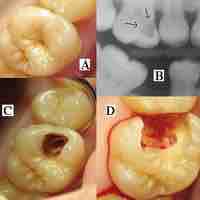

Dental caries cause demineralization of the hard tissues and destruction of the organic matter of the tooth.

Plaque-induced inflammatory lesions make up the vast majority of periodontal diseases, which are divided into peridontitis or gingivitis.